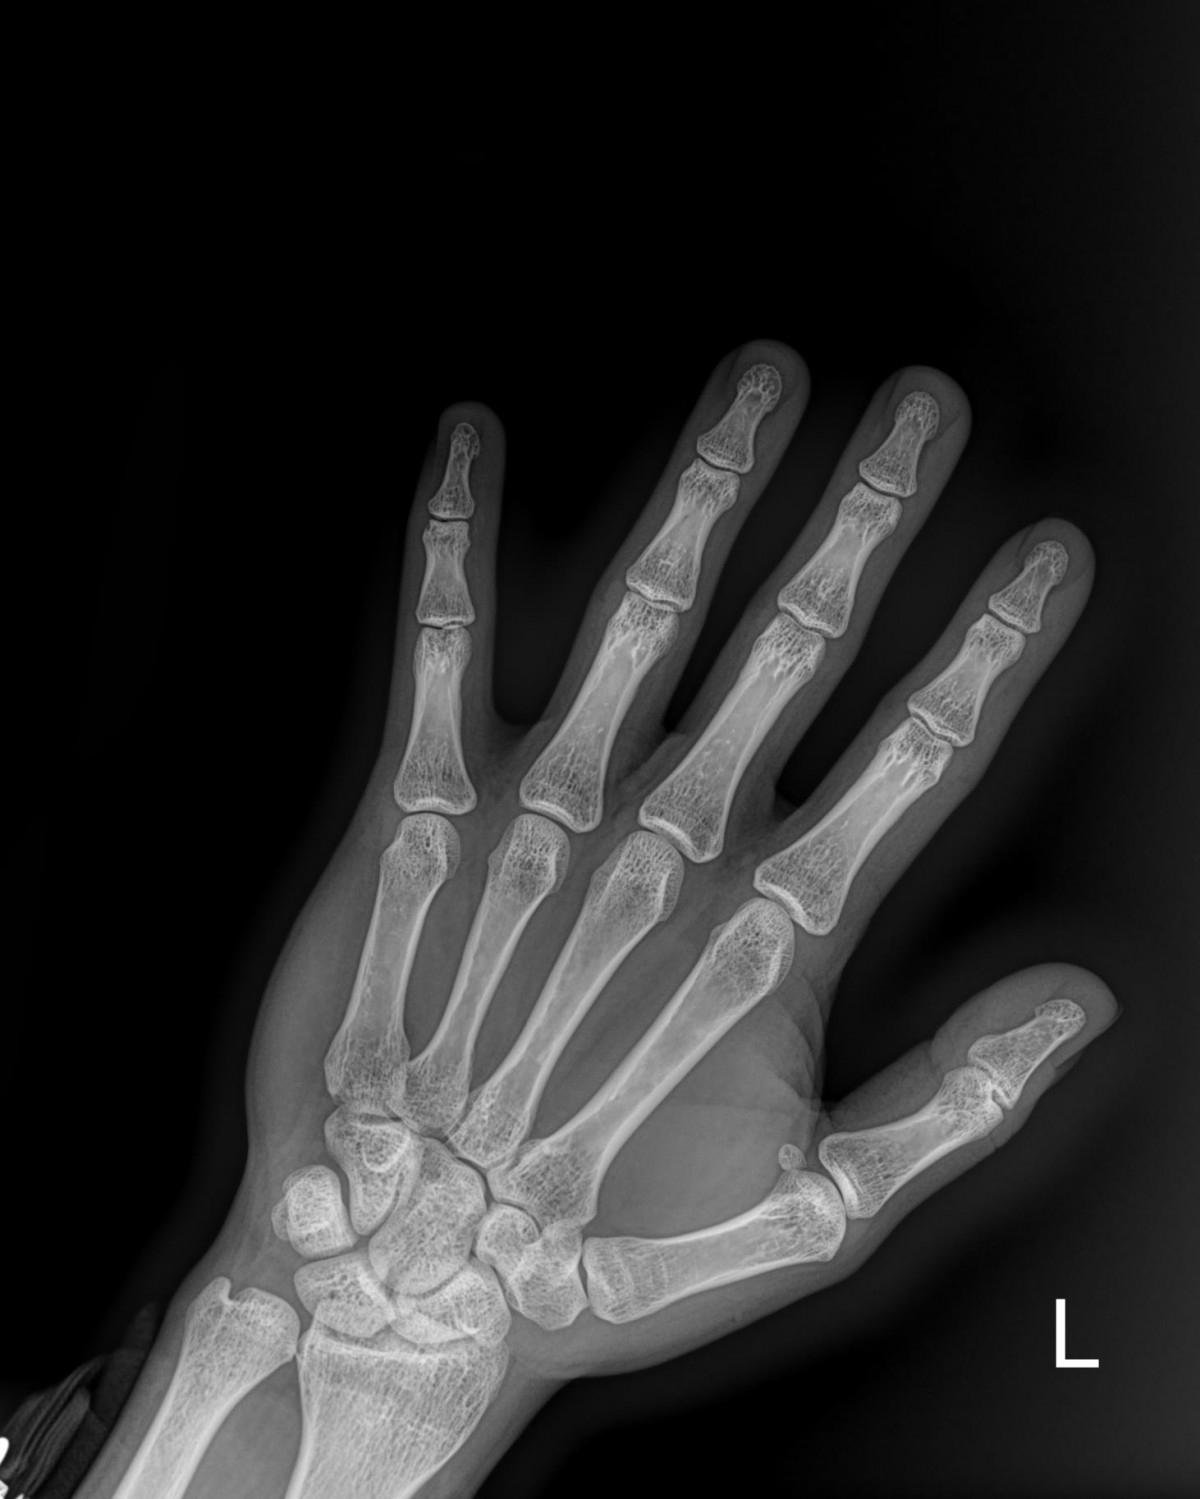

하윤원원장님 손가락 골절 수술 송형O 환자

작성자 최고관리자 댓글 0건 조회 2,207회 작성일 23-04-18 11:54